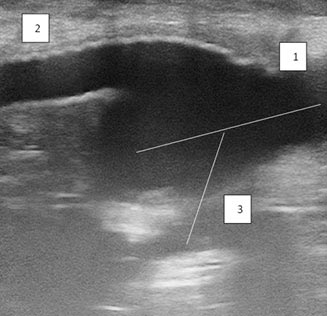

У пациентов группы В угол отхождения ГАБ составил 40–60°: у 10 (58,8%) пациентов он соответствовал 40°, у 7 (41,2%) пациентов — 50°. На 7-е сутки RI составил 0,84±0,18, к концу 1-го месяца — 1,04±0,11 (рис. 2).

Рис. 2. Дуплексная сканограмма области бифуркации общей бедренной артерии у пациента из группы В через 1 мес: 1 — общая бедренная артерия; 2 — синтетический протез; 3 — глубокая артерия бедра (угол её отхождения 60°)